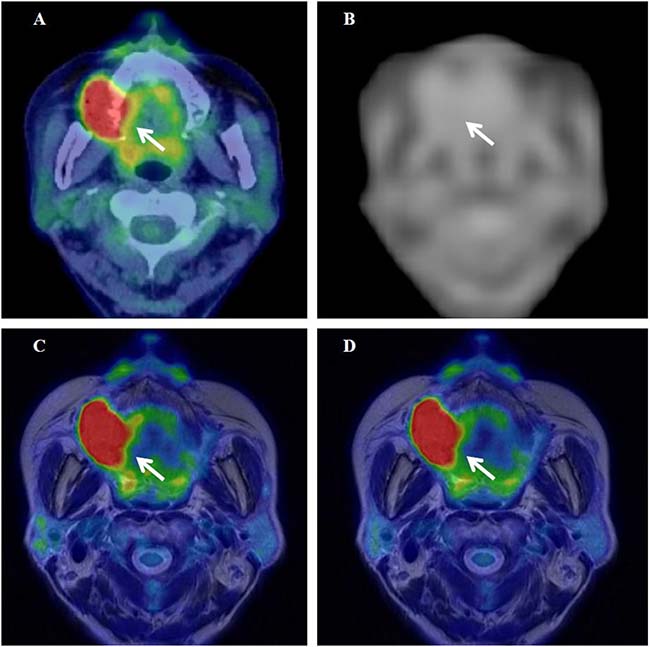

Representative cases of cervical cancer and oropharyngeal cancer are shown in Figures 5 and 6, respectively. Textural features were extracted using 64 bins (fixed bin width of 0.4 SUV) in these cases.

Figure 6: 18F-FDG PET/CT (A), the MRAC map (B), and PET/MR0-2min- and PET/MR0-10min-T2WI fused images (C and D) of a 67-year-old woman with stage IVA upper gingival cancer. Arrows show the primary tumor.

Figures 6A–6D show 18F-FDG PET/CT, the MR-AC map, and PET/MR0–2 min- and PET/MR0–10 min-T2WI fused images of a 67-year-old woman with stage IVA upper gingival cancer (#12 in Table 2), respectively. SUV of 14.0 on delayed PET/MR0–2 min images was slightly higher (2%) than that of 13.7 on early PET/CT images in this patient. The MR-AC map (Figure 6B) did not assign the appropriate μ value to the jaw bones, which may have resulted in insufficient AC underestimating tracer uptake on PET/MR images. SUV on PET/MR0–2 min images was similar to that on PET/CT images in the upper gingival cancer patient, possibly because the biological effect at the delayed scan period was canceled out by the gross underestimation of tracer uptake by MR-AC. The differences (|% difference|) observed in TMR, skewness, kurtosis, entropy, homogeneity, SRE, and LRE between PET/CT and PET/MR0–2 min were 29%, 63%, 14%, 7%, 10%, 0%, and 1%, respectively.